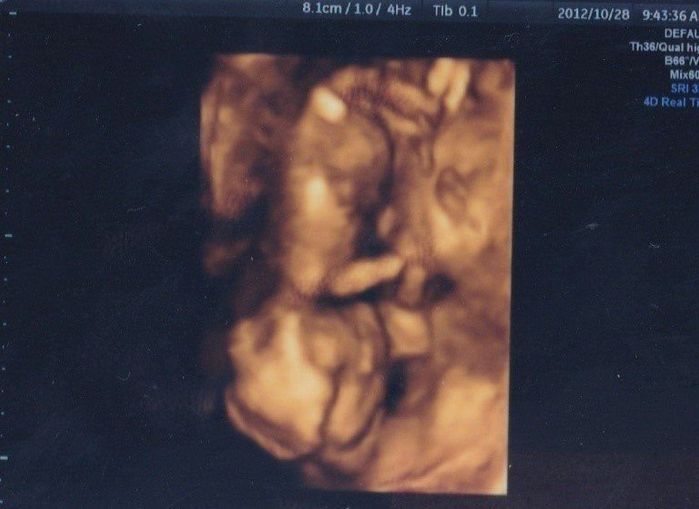

妊娠14週目のエコー写真

こちらは、4D写真です。頭を下にして反対側を向いていました。お顔が見たかったのに、向こう側を見て「指しゃぶりでもしているのかな?」腕もしっかり写っています。